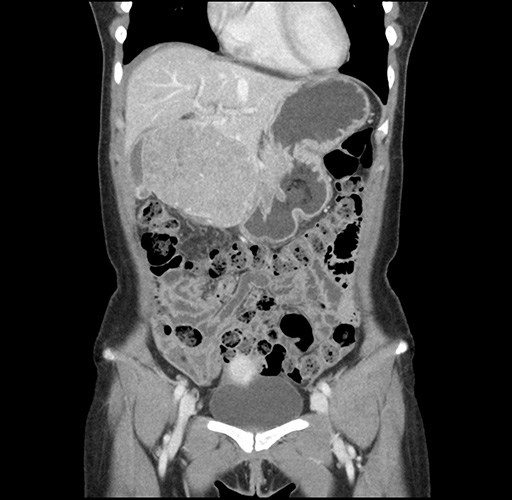

Imaging Analysis

Look through the patient's CT scan to identify any areas of concern for the necessary procedure.

Based on your CT findings, which issue(s) would give reason for "planned slowing down moment(s)" in this case?

Considering a standard left lateral sectionectomy procedure, what step(s) of the operation would you do differently in this case ?